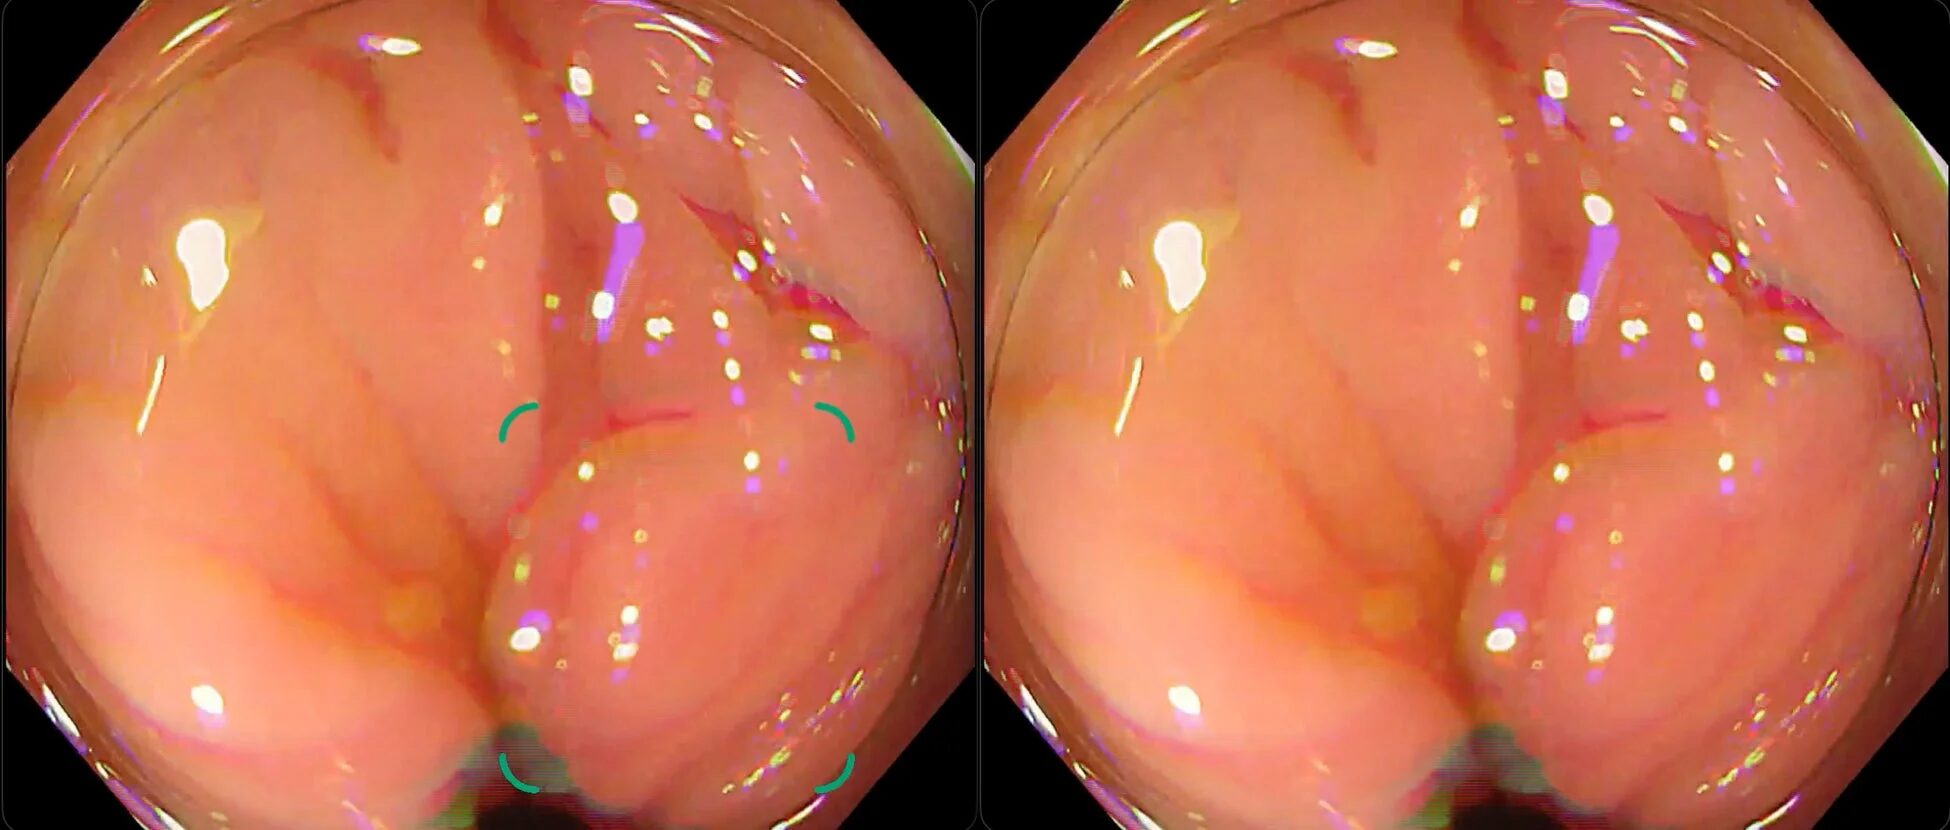

新モデルがどれだけ賢くなったのか、具体的な検出事例を見てみましょう。特に、これまで偽陽性の原因となっていた「残渣」「ひだ」「泡」による誤検出が改善されている点が注目されます。

① 残渣による偽陽性が改善した例

左の旧モデルでは、消化管内の残渣をポリープ候補として検出してしまっていますが、右の新モデルではそれが改善され、真のポリープ候補に集中できるようになっています。

② ひだによる偽陽性が改善した例

大腸のひだは、影になったり形がポリープに似て見えたりすることがあります。旧モデルではひだを誤検出していましたが、新モデルではこのような判断ミスが減っています。